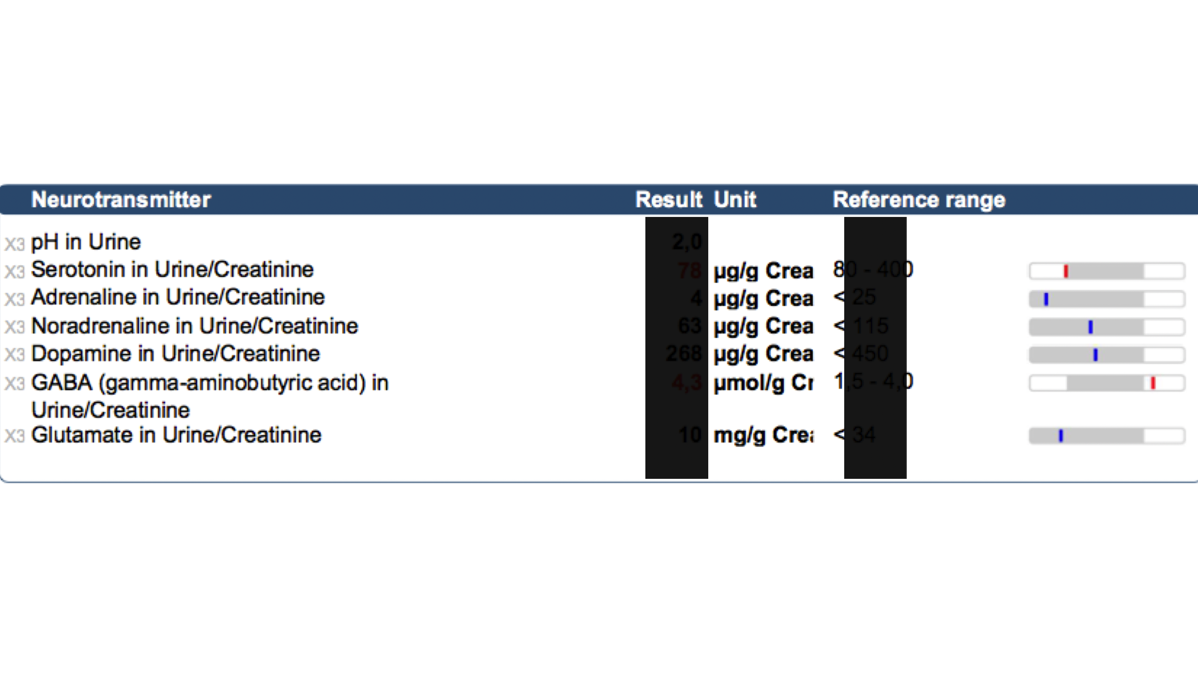

神経伝達物質検査

同時にセロトニンやアドレナリンなどの神経伝達物質を測定する。気持ちを鎮めたり、昂らせる神経伝達物質の不均衡の具合が判明し、再び均衡を得るための食事内容やビタミン、天然物質などの選択に役立つ(海外検査機関送付)。